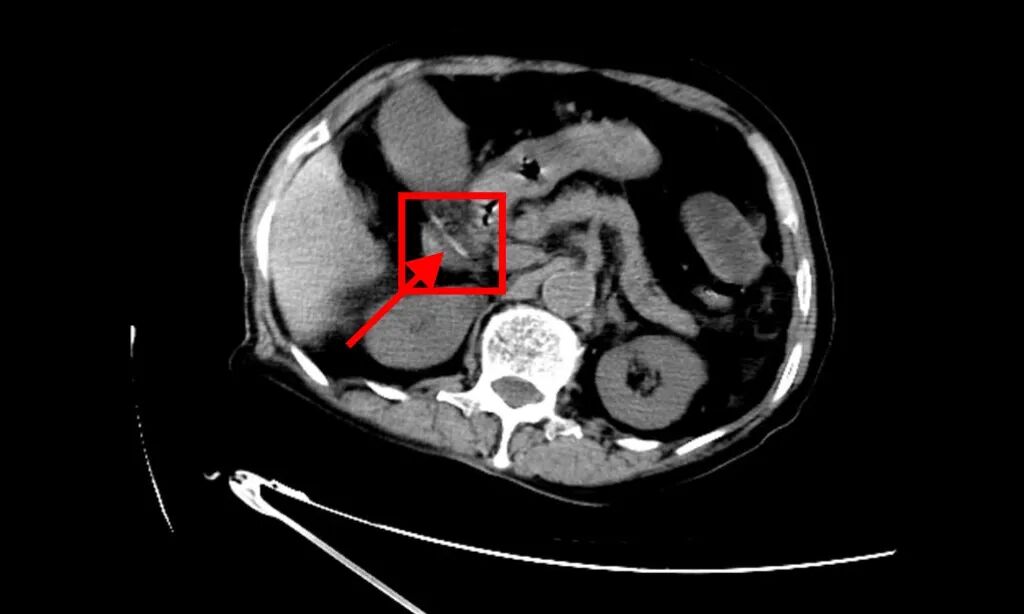

急诊医生迅速开单检查。腹部立位片提示:消化道穿孔可能。随后的腹部CT,给出了更明确的答案——十二指肠水平部有管状高密度影并见游离气体,考虑“消化道异物伴穿孔”!

▲腹部CT发现消化道异物